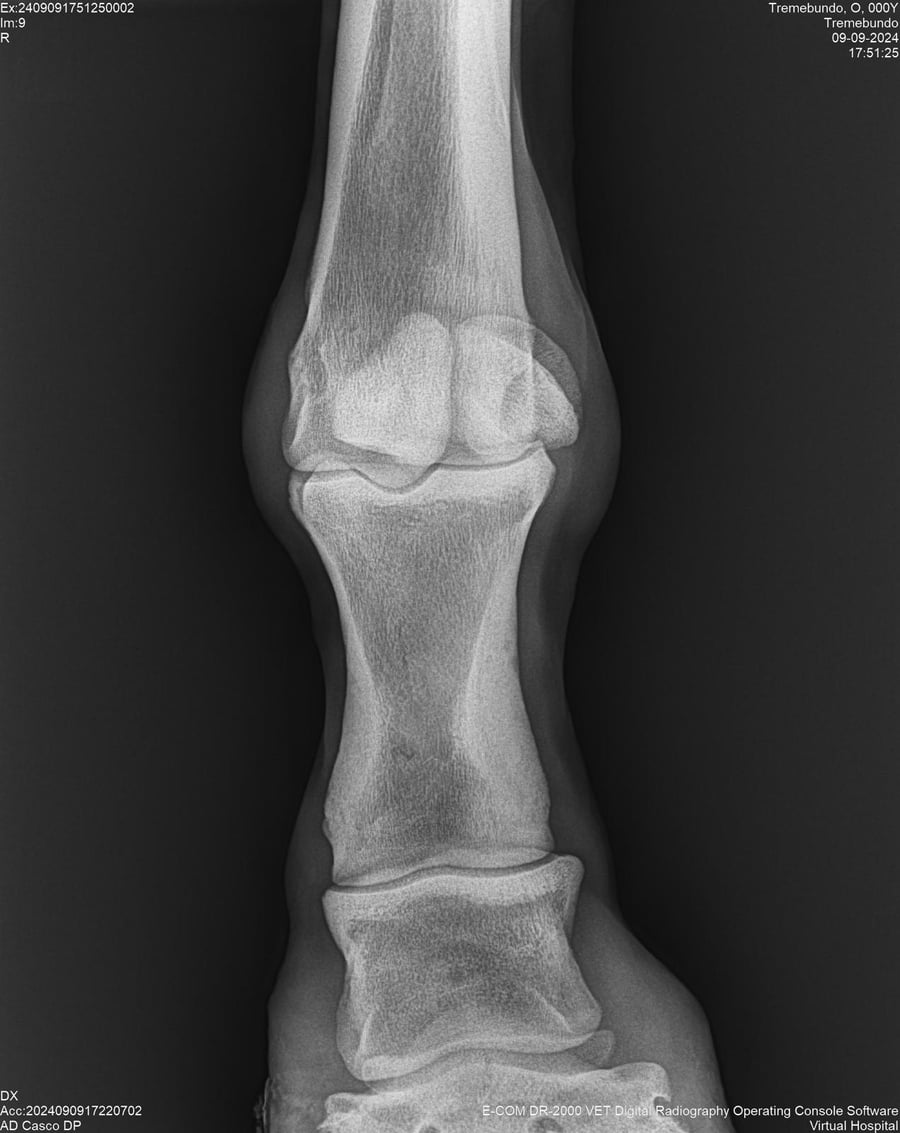

LOTE 37, TREMEBUNDO

Identificador: #291140-

Generacion 2022